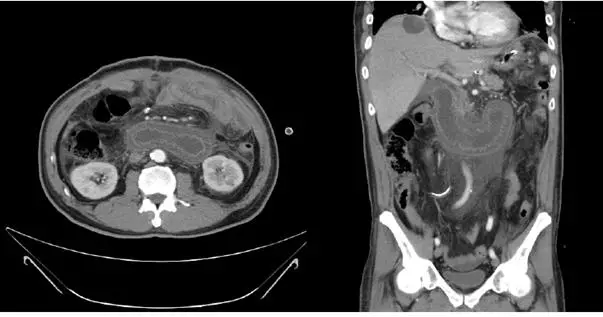

電腦斷層顯示軸切面(axial)與冠狀切面(coronal)兩組影像。

軸切面所見: 右上腹可見一個巨大、液體充填(fluid-filled)的管狀結構,位於胰臟頭部周圍,形成特徵性「C 字形(C-loop sign)」。此液體充填管腔壁薄、無氣體充填(no oral contrast opacification),腸壁可見 valvulae conniventes(鍵盤徵,keyboard sign)向腔內突出,可與胰臟假囊腫(pancreatic pseudocyst)鑑別。腸腔極度擴張,管徑明顯增大(約 5 cm 以上)。

冠狀切面所見: 右上腹至中腹可見連續性擴張的液體充填腸管,跨越中線延伸,繞行於腸系膜血管與主動脈之間。上方可見胃及吻合口,擴張的輸入腸端(afferent limb)積聚大量膽汁、胰液及腸液,無法順利排入胃。骨盆腔及腹壁外觀尚無明顯腹水或游離氣體。

影像結論: 上述電腦斷層表現符合急性輸入腸端阻塞(acu